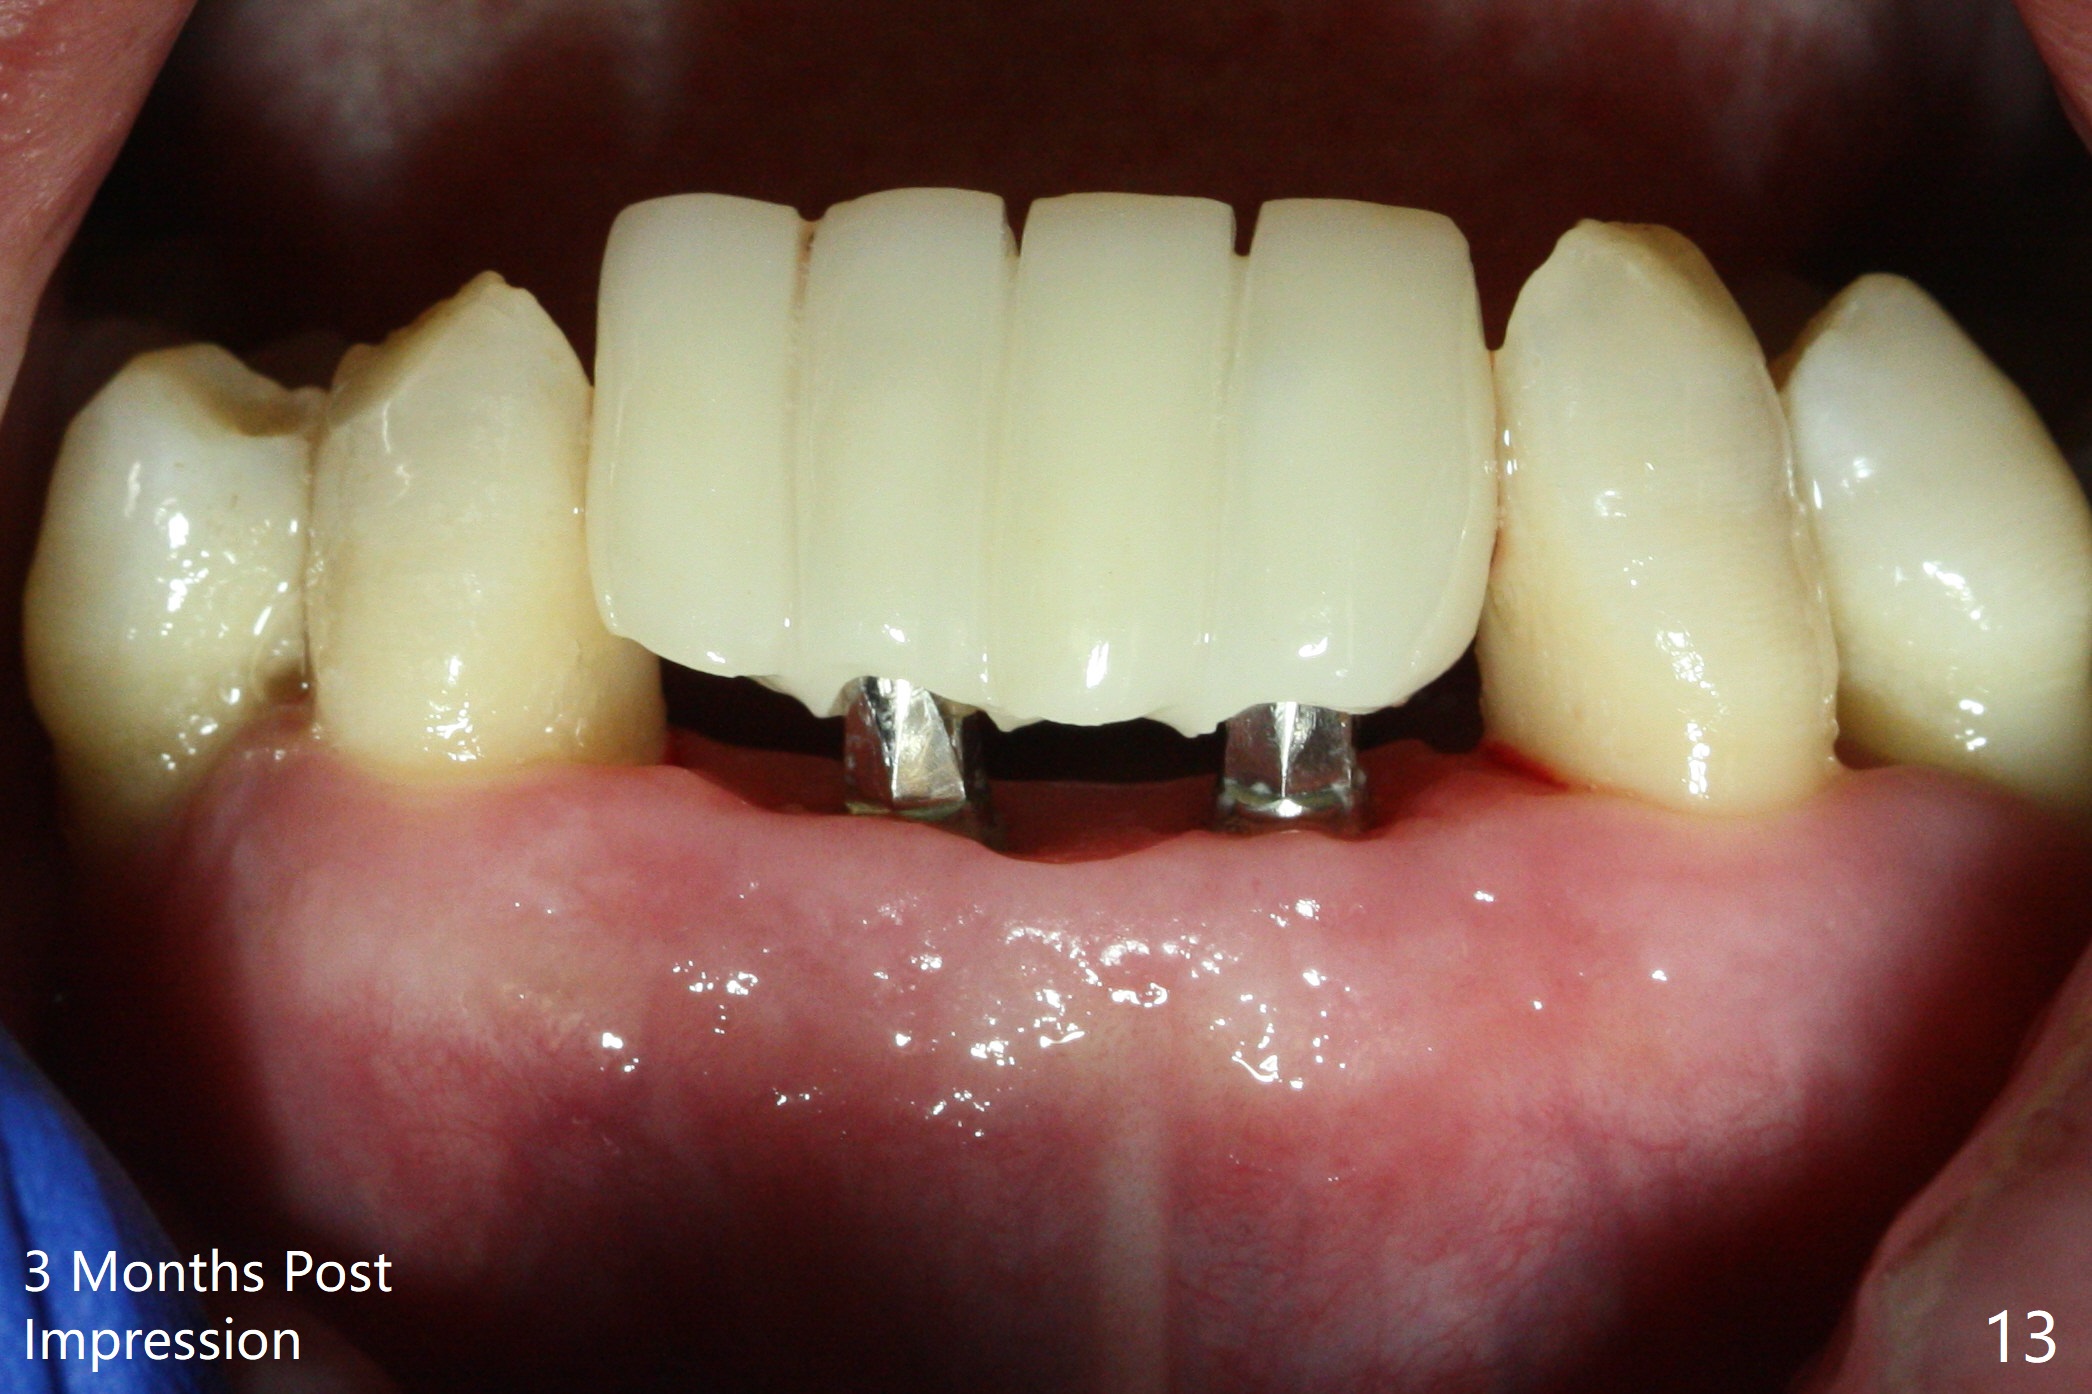

After extraction of 4 of the lower incisors, there are basically 2 sockets (#23/24 and 25/26), separated by the apparently midline bone (Fig.1 red line).  In spite of using Lindamann bur to move the 25/26 osteotomy mesially, a 3x14(2) mm dummy implant remains close to the tooth #27 (Fig.2).  The terminal branch of the Incisive Canal (<) is located between the lateral and central incisors.  A de novo osteotomy (Fig.3 (1.5 mm drill)) is made mesial to the original one (O).  While the 3x14(2) mm dummy implant is incompletely placed at #25/26, a 3x14(4) mm 1-piece one is placed at #23/24 (Fig.4).  Finally the same implant is placed at #25/26 with placement of mineralized cortical/cancellous bone (Fig.5 *).  When the large sockets are sutured, the supraerupted teeth #7-9 touch the lower gingiva (Fig.6).  The incisal edge is reduced for clearance (Fig.7).  Periodontal dressing is less likely to be dislodged with the incisal edge reduction (Fig.8,9).  A provisional FPD is fabricated 1 week postop.  Hard (Fig.10) and soft (Fig.11,12) tissues heal 5.5 months postop.  The patient returns for crown cementation 3 months post impression (9 months postop, Fig.13,14).